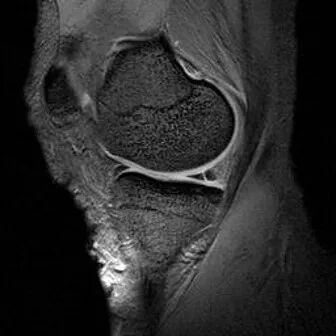

半月板水平撕裂

1、水平撕裂

2、较少见3、III级高信号与胫骨平台平行,到达半月板的游离缘或一侧关节面

(半月板水平撕裂)